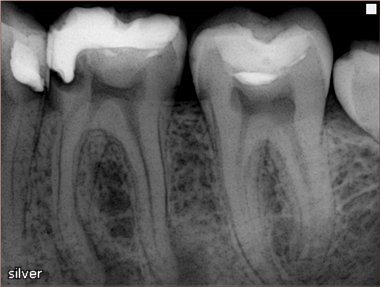

Рентгеновские снимки кариеса корня зуба

Раздел: Визуальные уроки